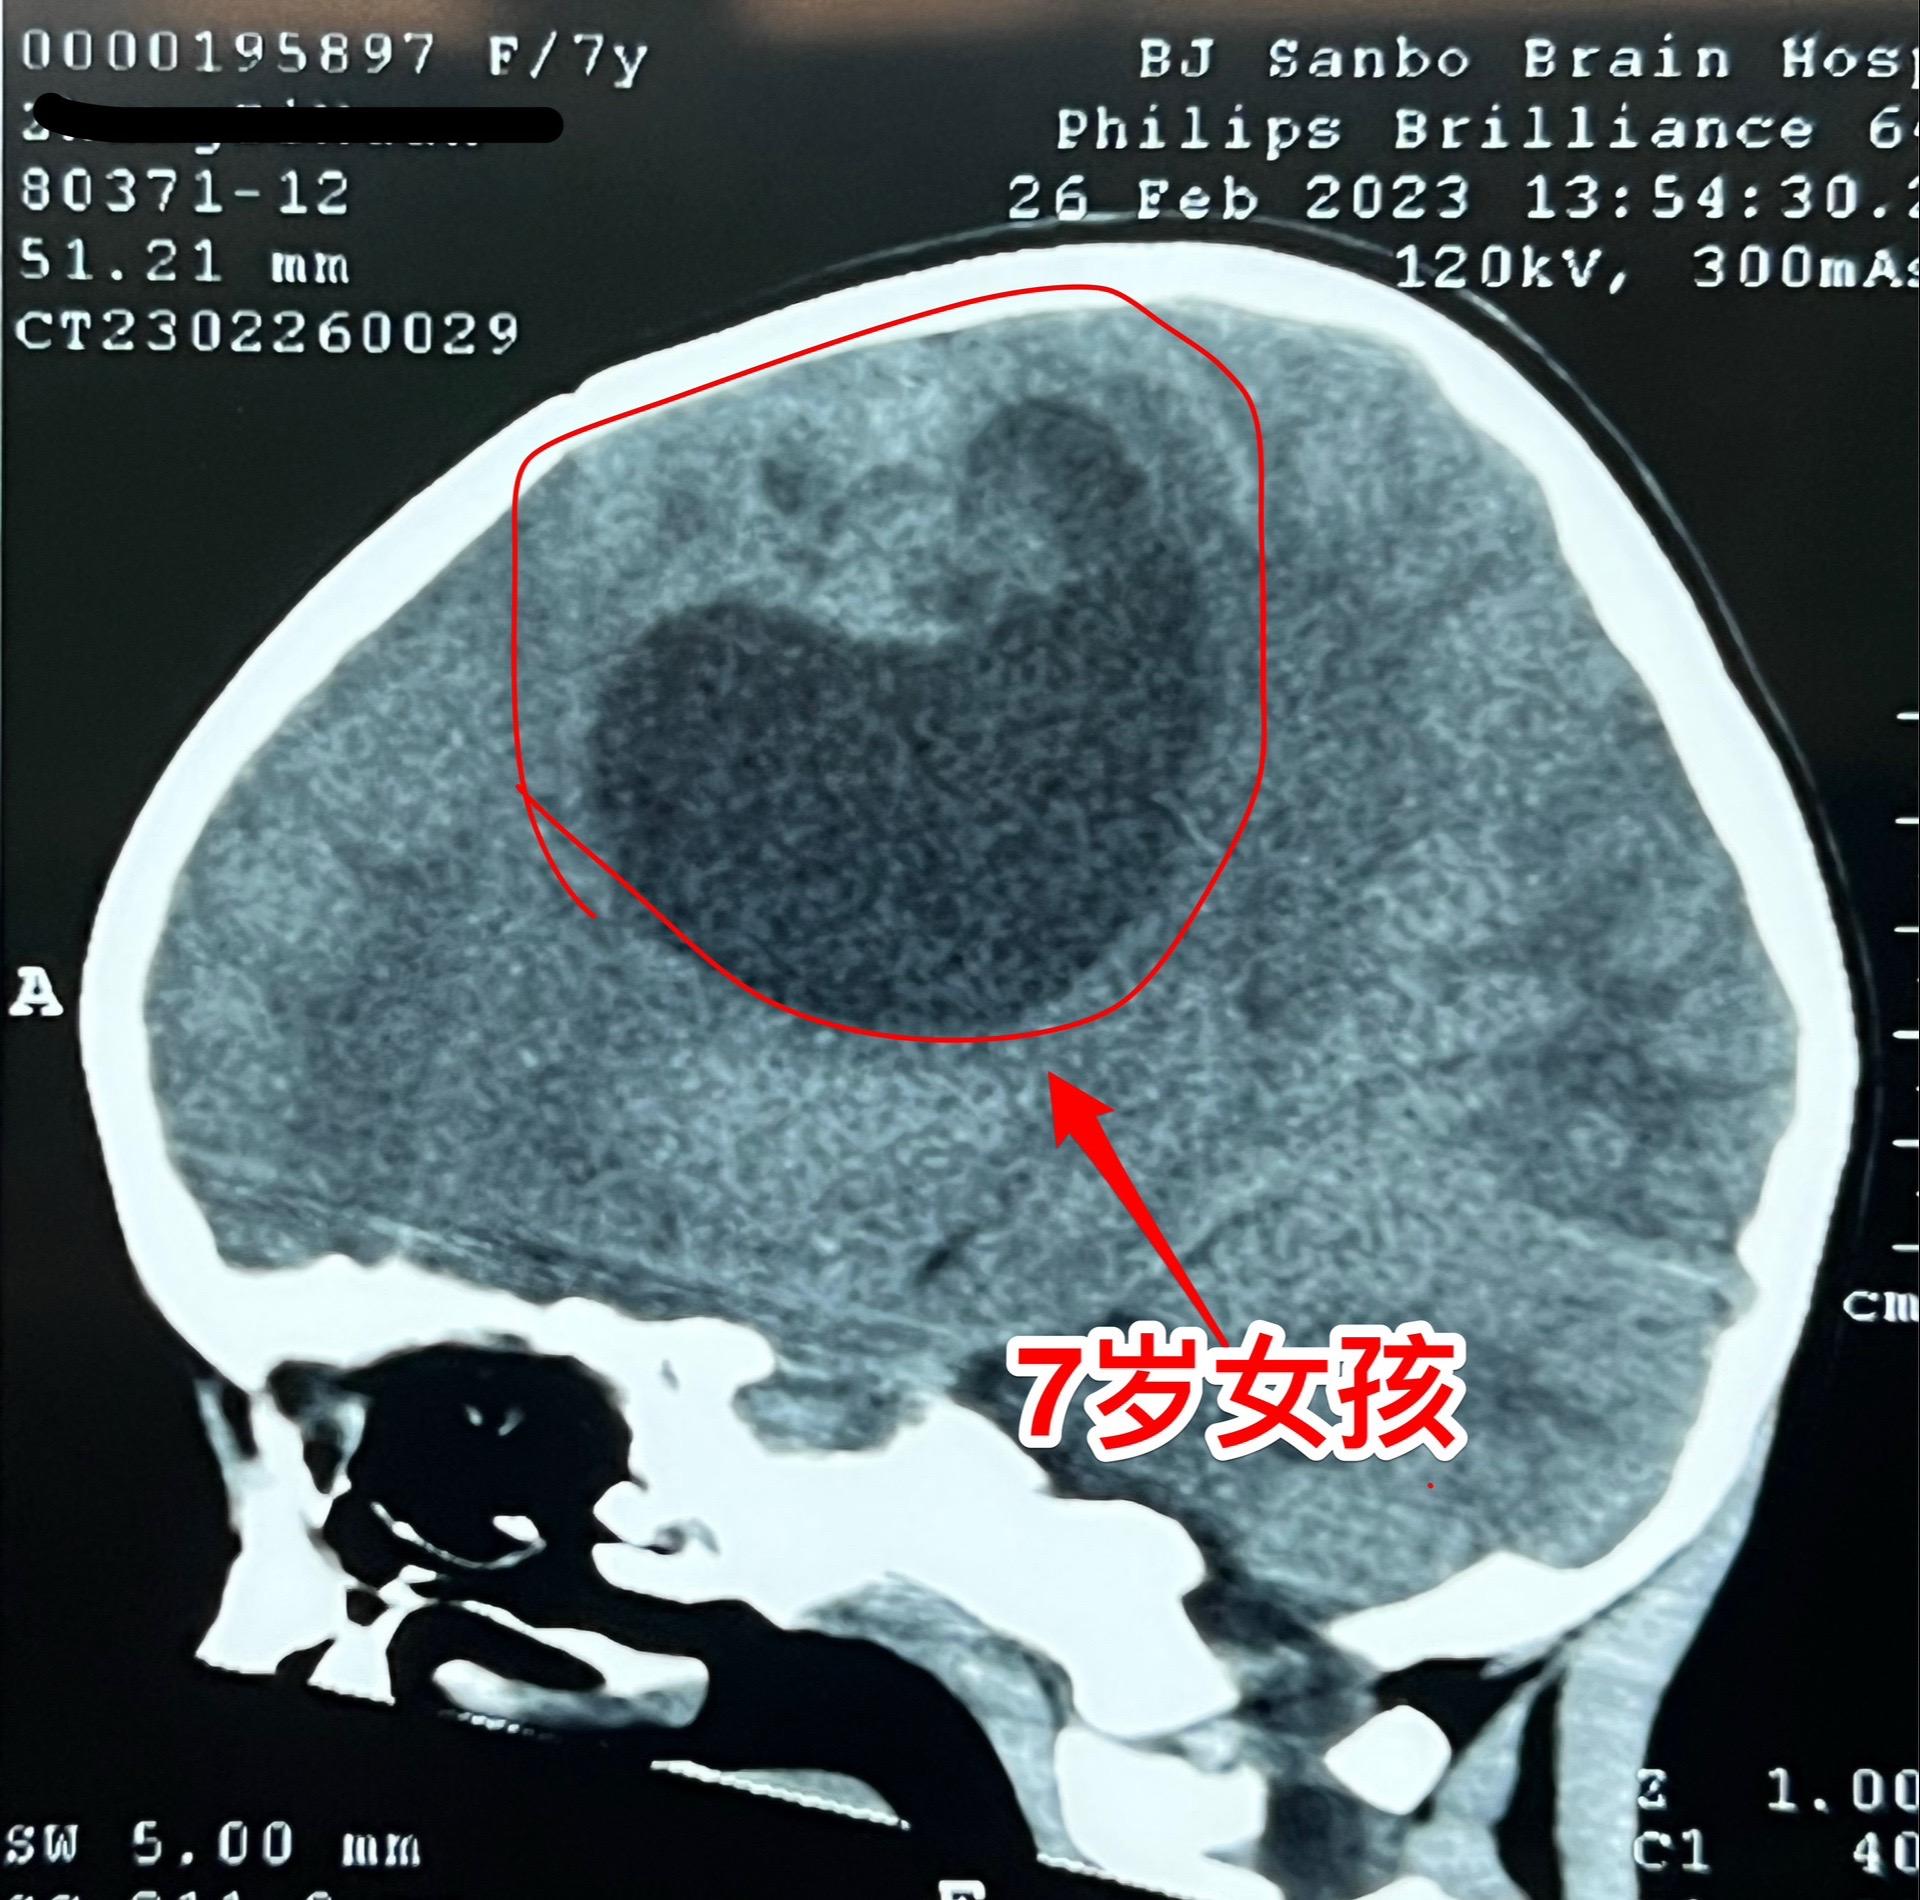

高级别胶质瘤手术后22个月,定期复查。2023年2月28日邯郸市7岁的小女孩因右侧上下肢无力在我科行开颅手术,切除左侧大脑的巨大肿瘤。如图所示,肿瘤体积巨大,手术后小女孩右侧上下肢无力症状明显改善。 病理报告为神经上皮肿瘤WHO三级。手术后作了全脑放疗。 今天是手术后22个月复查,肿瘤没有复发,小孩子的四肢活动无力弱,能正常上学。磁共振显示肿瘤没有复发,以后还要定期复查。